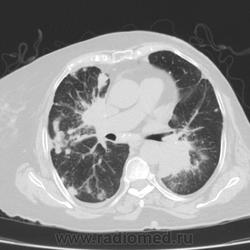

Метастатическое поражение легких.

Пожилая женщина, 76 лет находится на стац.лечении, провели СКТ дообследование.  Сопут- сr левой молочной железы. Такие множественные

поражения  в легких встречаются не часто.

Раннее несколько лет назад оперирована по поводу рака левой молочной железы.

Не всё на снимках видно. Многое осталось бы за кадром.